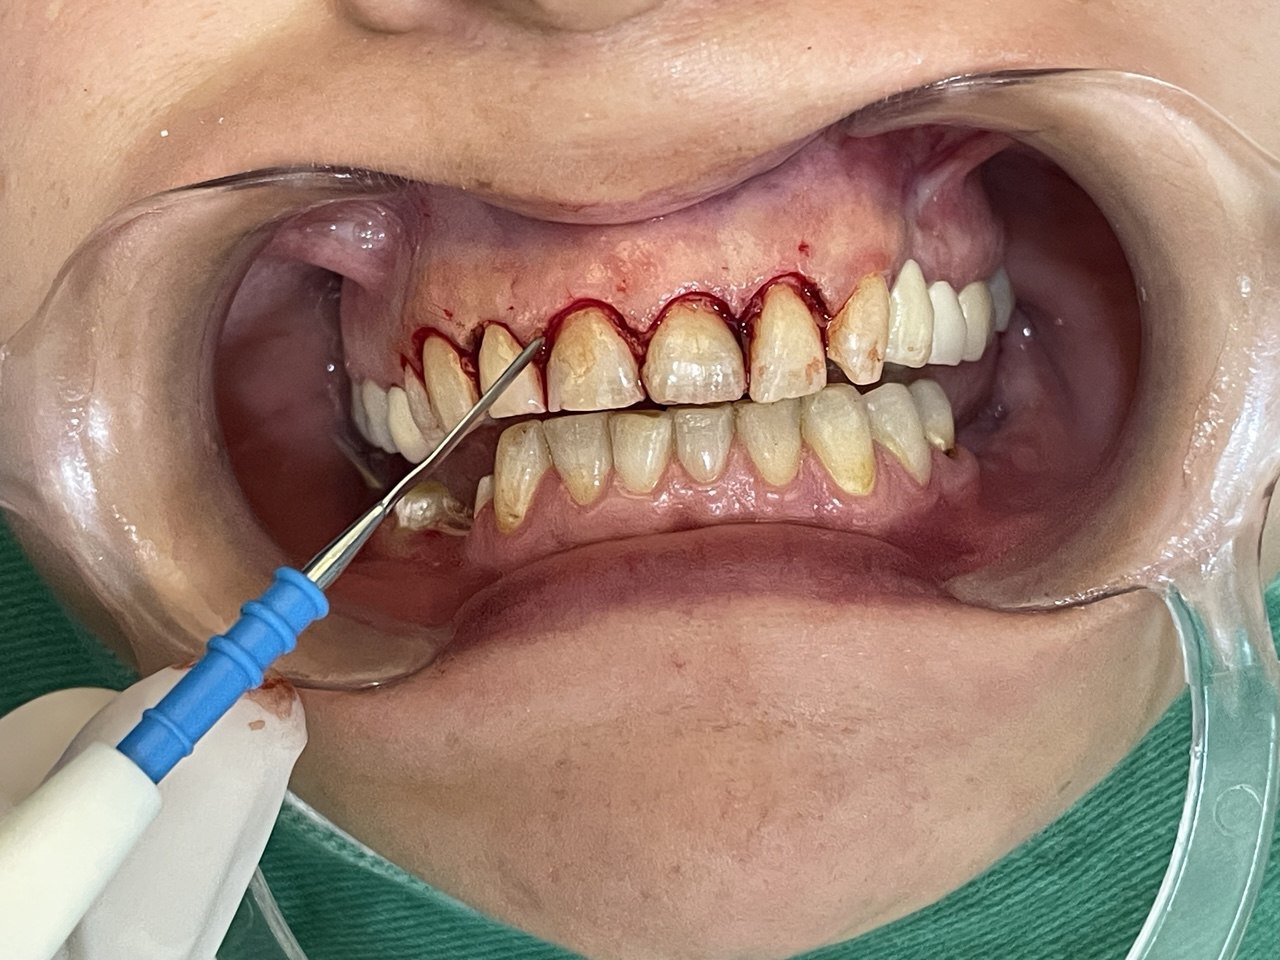

This hereditary condition is caused by aggressive bacteria that attack and destroy the alveolar bone surrounding the roots of the teeth. The bone loss may be moderate or severe, leading to:

Complete root exposure in advanced cases.

Frequent gum bleeding.

Surgical treatment is required to halt the progression of the disease and preserve the remaining teeth, though natural bone regeneration is not typically possible at this stage.